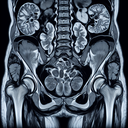

МРТ органів малого тазу

МРТ (магнітно-резонансна томографія) органів малого тазу - це неінвазивний метод діагностики, який використовує магнітні поля та радіохвилі для отримання детальних зображень внутрішніх структур малого тазу. ### Коли призначають МРТ органів малого тазу 1. **Оцінка репродуктивних органів:** - Для діагностики патологій матки, яєчників у жінок...